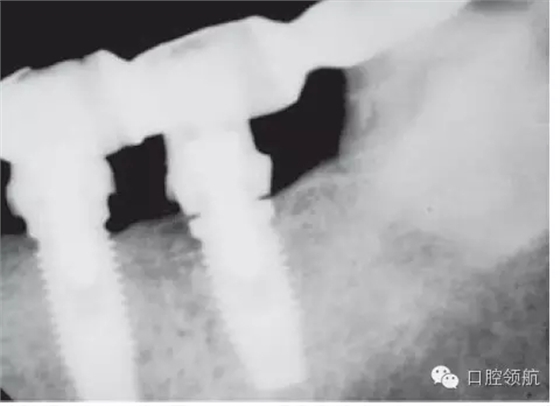

另外一個(gè)方面,深的袖口將妨礙修復(fù)體完全就位(圖9.26)。通常可以通過放射學(xué)檢查,確認(rèn)修復(fù)部件的就位情況,包括種植體與基臺(tái)的連接部分。即使是內(nèi)連接,轉(zhuǎn)移體或者其他修復(fù)部件也會(huì)因深袖口而不能就位。以下技術(shù)可以用于解決這些問題:可以在局部麻醉下,插入喇叭狀或者外展的基臺(tái),以非手術(shù)的方式擴(kuò)大袖口(圖9.27 a,b),然后再通過放射學(xué)檢查確定部件的完全就位。組織會(huì)受壓發(fā)白,15分鐘后,軟組織將會(huì)擴(kuò)張,以允許理想修復(fù)部件的就位,這樣治療將得以繼續(xù)。有時(shí),需要在鄰面做兩個(gè)小切口,以緩解袖口軟組織張力(圖9.28 a,b)。通常不需要縫合。一旦袖口組織塑形完成,可運(yùn)用最佳塑形的臨時(shí)(圖9.29)或最終部件(圖9.30),來維持理想的軟組織外形。

圖9.26 放射學(xué)影像顯示,在外六角連接的種植體上,基臺(tái)沒有完全就位。